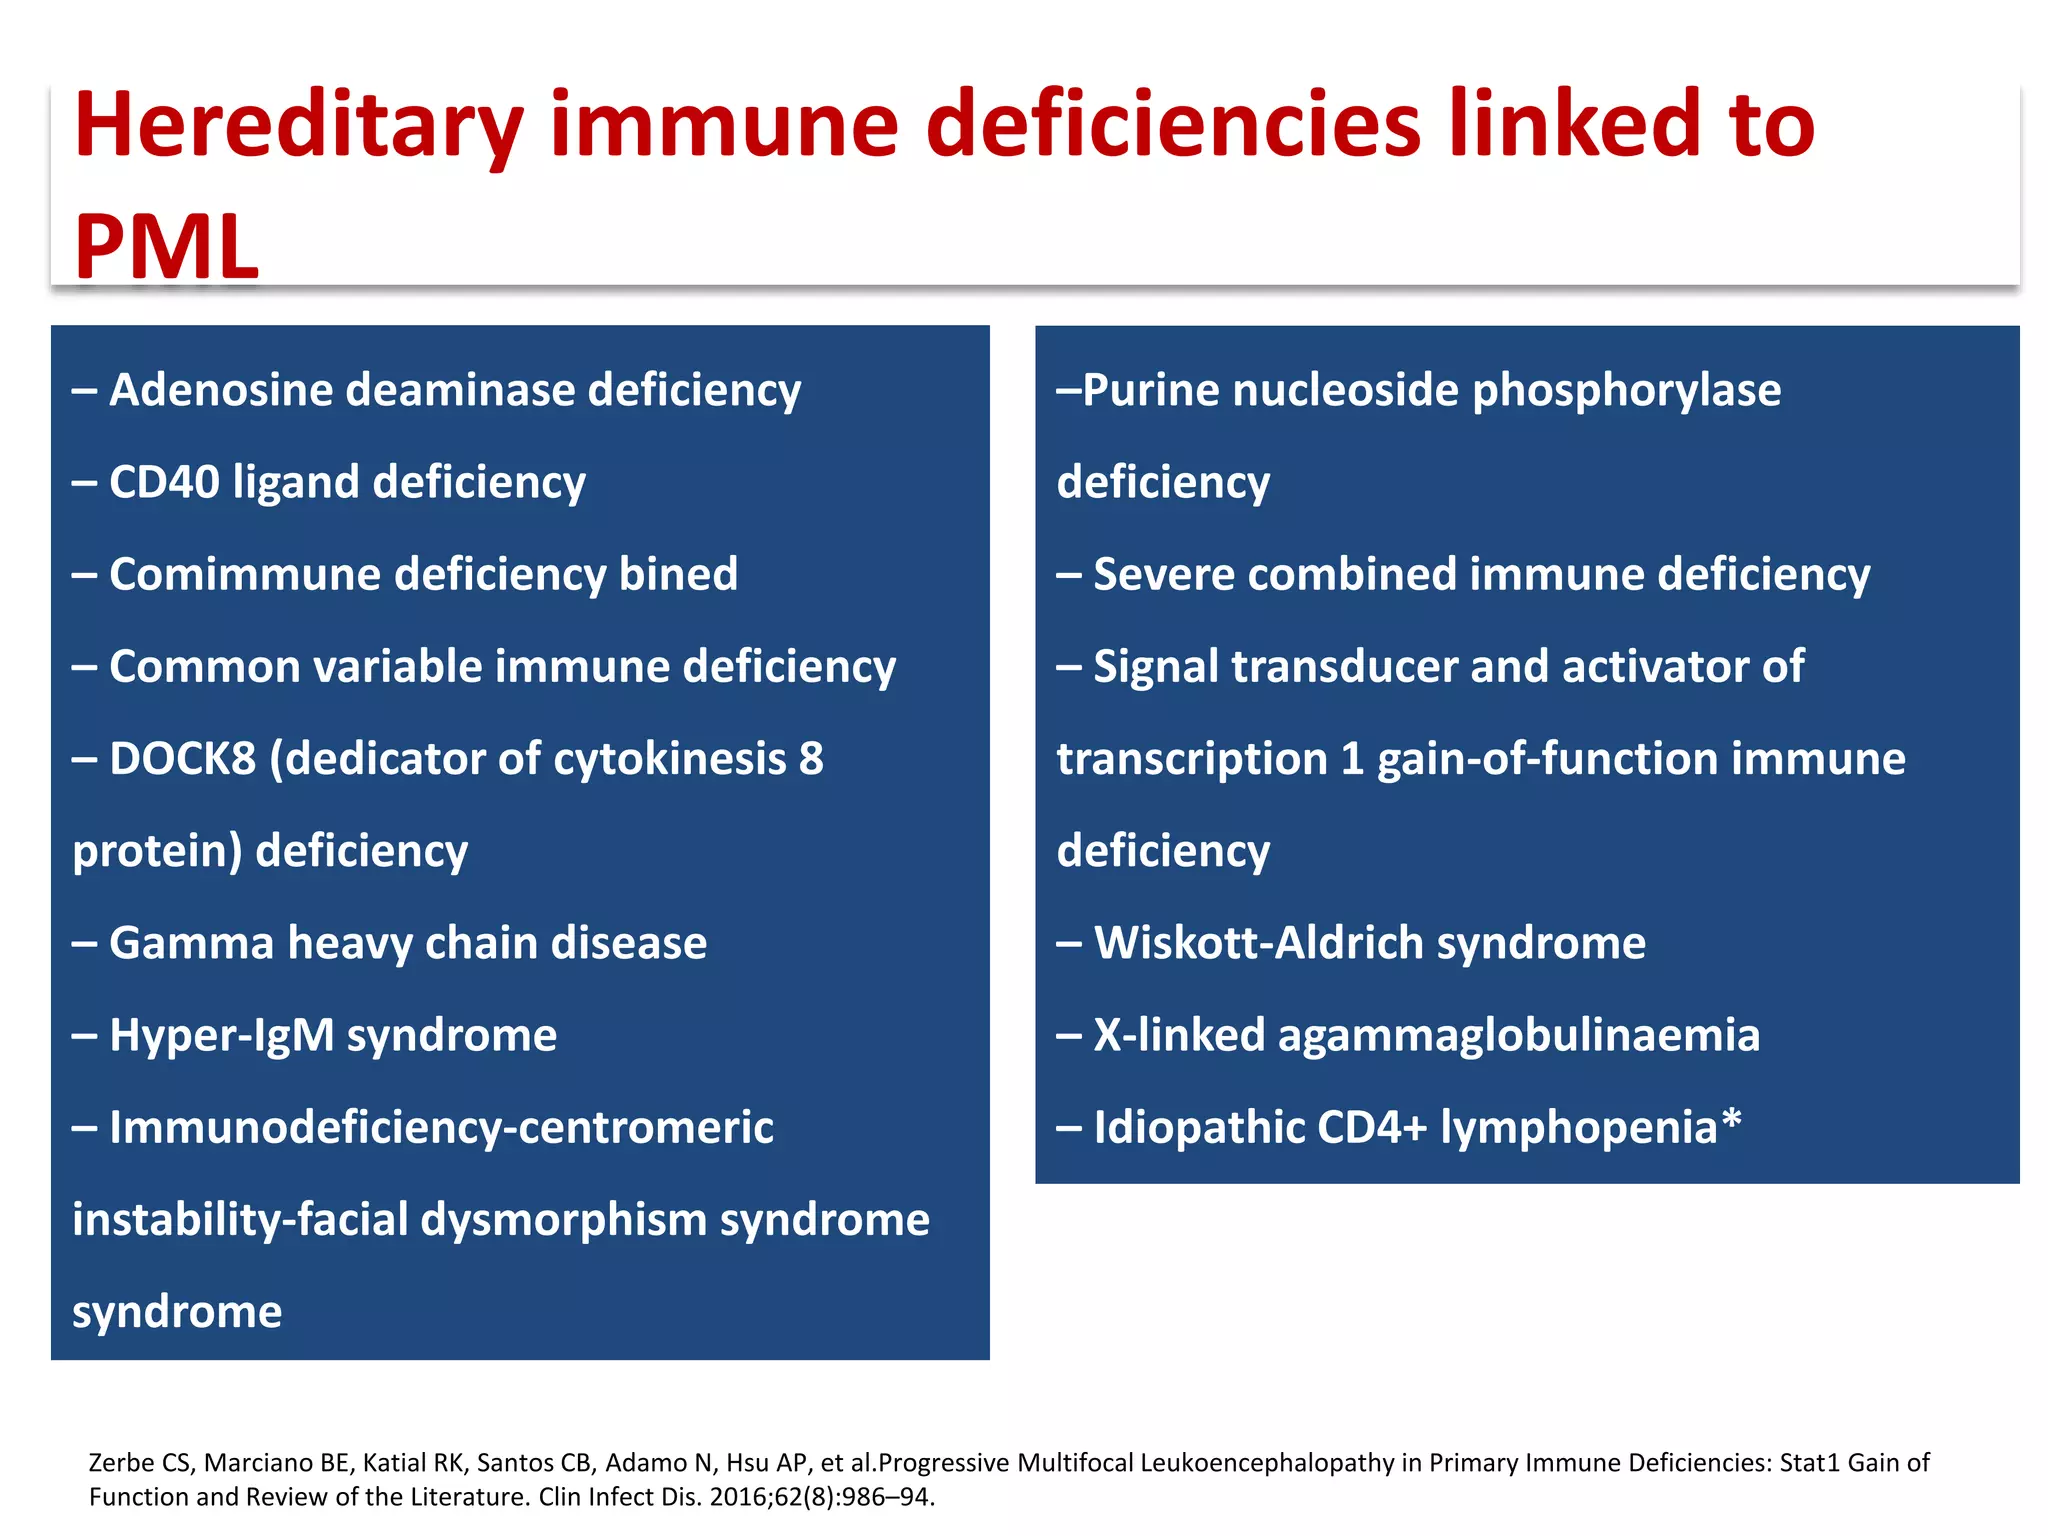

This document discusses progressive multifocal leukoencephalopathy (PML), an opportunistic infection caused by the John Cunningham virus (JCV) that leads to demyelination in the central nervous system. It highlights the epidemiology, clinical manifestations, diagnostic methods, and risk factors associated with PML, particularly in immunocompromised patients and those undergoing immunomodulatory therapies. It also presents data on the incidence of PML in patients treated with natalizumab and other therapies, addressing the relationships between these treatments and the development of PML.